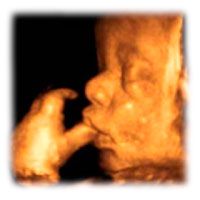

36 неделя беременности рост и развитие малыша

Ребенок подрос уже до 46 см, а вес его на 36 неделе обычно составляет 2,7 кг. Правда, вес на малыша этой неделе может отличаться в ту или иную сторону, связано это с наследственностью и другими внешними причинами. К концу этой недели твой ребенок уже будет считаться полностью доношенным, как и все детки, которые появляются на свет на 37-42 неделях беременности. После 42 недель ребенок считается переношенным, а до 36 недели – недоношенным. Большинство малышей на 36 неделе находятся в головном предлежании, если это не так, врач может предложить перевернуть ребенка руками. Взвесь все «за» и «против», прежде чем соглашаться на процедуру, так как этот способ может привести к преждевременным родам и придется ургентно проводить кесарево сечение.